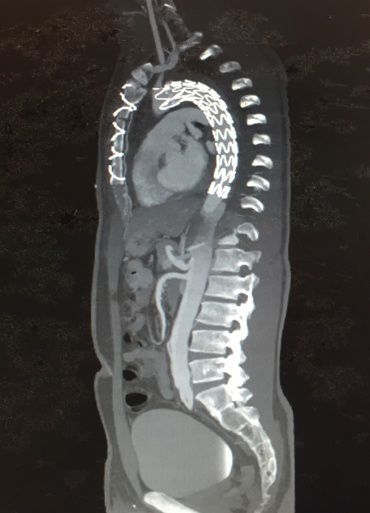

结合王先生的实际情况,心血管内科黄铮主任认为,单纯的主动脉腔内隔绝术或联合“烟囱”技术等都不是该患者的最佳治疗方式,建议联合心脏外科一同会诊。经过心血管内科与心脏外科的专家会诊讨论之后,决定联手为王先生开展一场“杂交手术”——左锁骨下动脉转流+右锁骨下动脉转流+主动脉腔内隔绝术,一起拆除这颗不一般的“血管炸弹”。

但是,“杂交手术”对医护团队配合度的要求非常高,需要外科手术与内科介入的无缝连接。首先,由心脏外科谢少波主任、王凯教授团队先为王先生实施了全麻下“右锁骨下动脉转流+左锁骨下动脉转流”,利用一根“Y”型人工血管将左、右锁骨下动脉与升主动脉相连接,完成双侧锁骨下动脉重建,确保患者双侧上肢的血供。

在此基础上,黄铮教授带领王慧勇博士等心血管内科介入团队进行了微创“主动脉腔内隔绝术”,成功植入主动脉覆膜支架,封堵主动脉夹层破口。术后,王先生被送入心血管内科监护室,在医护人员的严密监护和精心治疗下,恢复良好,双侧上肢活动正常,血液供应完全没有受到影响,2月27日已经转入普通病房。